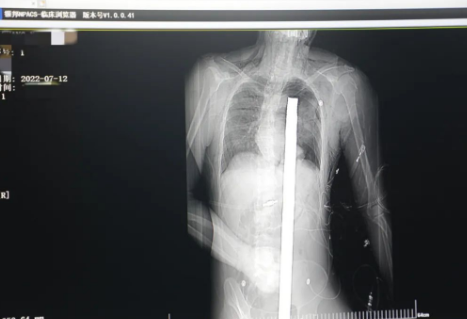

突發(fā)!太疼了,1.2米長的螺紋鋼從男子會陰部垂直穿入胸腔......7月12日下午16時(shí)10分,西安一處工地的一名26歲工友,不慎從10多米的高空墜落,不幸的是工地上一根直徑3厘米的螺紋鋼從男子會陰部垂直穿入體內(nèi),工地上的工友們小心翼翼地將連著的鋼筋截?cái)唷G闆r危急,立即送往西安國際醫(yī)學(xué)中心醫(yī)院急救中心,此時(shí)正是下午17時(shí)00分。

時(shí)間就是生命!此時(shí),西安國際醫(yī)學(xué)中心醫(yī)院展開了一場與生命賽跑的搶救,第一時(shí)間開辟綠色通道,急診X光片及CT顯示:異物經(jīng)會陰部貫穿盆腔、腹腔到達(dá)左側(cè)胸腔主動脈弓水平。醫(yī)院創(chuàng)傷中心立即啟動應(yīng)急預(yù)案,劉延彤副院長親臨指揮,下午17點(diǎn)48分,當(dāng)患者被送達(dá)手術(shù)室,胸外、心外、肝膽外科、胃腸外科,泌尿外科及麻醉科等多學(xué)科專家聯(lián)手對這名工友進(jìn)行“縱劈胸骨 前外側(cè)開胸探查 氣管及主支氣管修補(bǔ) 肺修補(bǔ) 血胸清除 開腹探查止血 腹膜后及盆腔探查......”手術(shù)。

情況緊急!術(shù)中探查后發(fā)現(xiàn),長120cm直徑3cm的螺紋鋼經(jīng)患者右側(cè)會陰部穿入,傷及直腸,途徑膀胱后方,左側(cè)髂總動靜脈之間傷及左腎后,經(jīng)胰腺后方在肝脾之間穿破膈肌,在下肺靜脈前方穿入左肺穿破氣管及左右主支氣管膜部,止于主動脈弓下水平,穿入體內(nèi)的部分達(dá)到75cm。